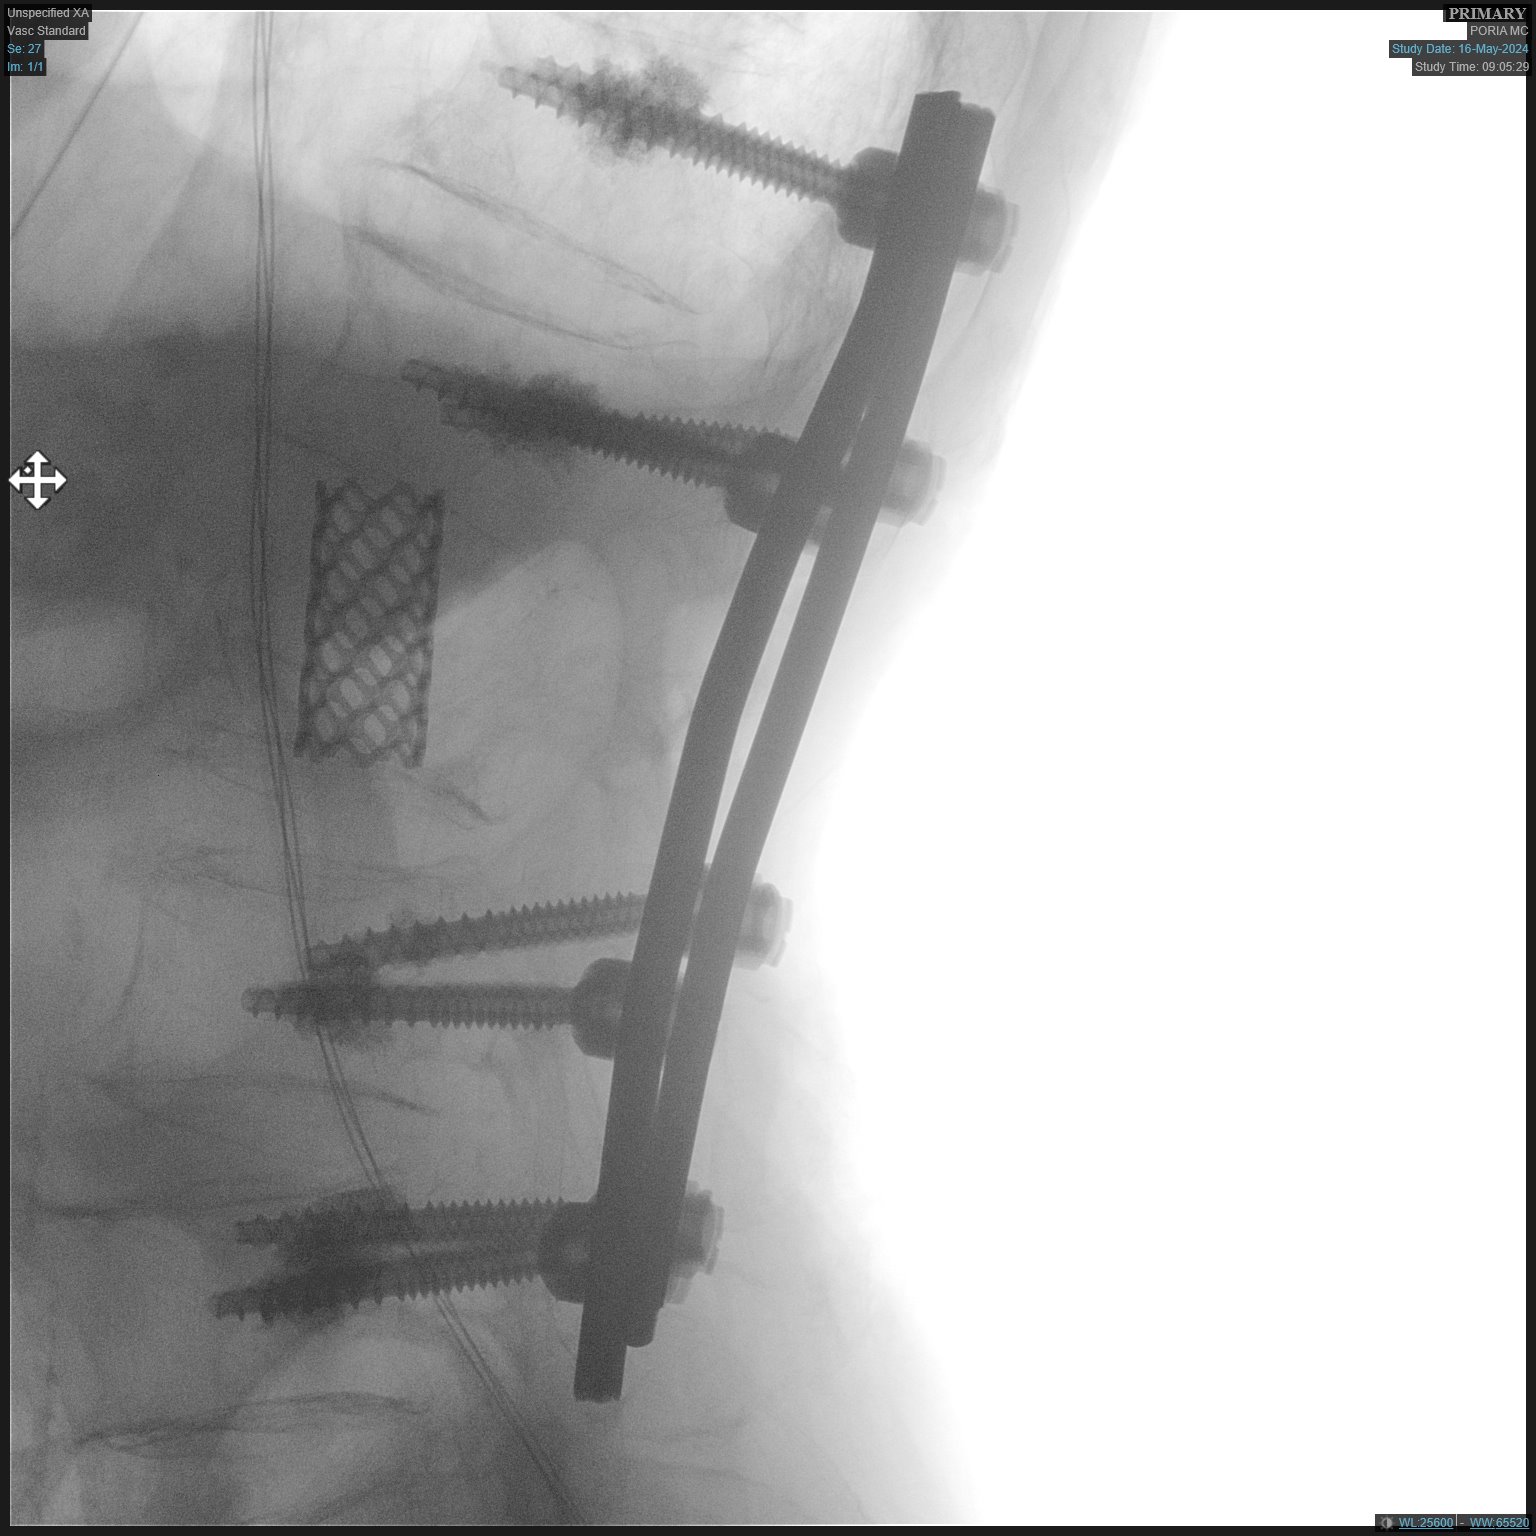

أجريت في المركز الطبي " تسفون" - " مستشفى بوريا "، في الشهر الأخير وللمرة الأولى، عملية جراحية لاستئصال غضروف من العمود الفقري من خلال عملية جراحية تجرى في منطقة الظهر للمتعالج.

وقالت متحدثة بلسان المستشفى " انه من النادر ما يتم إجراء هذه العملية الجراحية في إسرائيل، لأنه فقط في حالات استثنائية يتطلب هذا النطاق الملحوظ من الاستئصال الجراحي. ويُجرى هذا النوع من العمليات الجراحية في عدد محدود من المستشفيات في البلاد، حيث تم إجراؤها بنجاح من قبل الدكتور ليئور ماروم، مدير وحدة جراحة العمود الفقري في المركز الطبي ( تسفون )".

وقال الدكتور ليئور ماروم فيما يتعلق بهذه الحالة: "بعد إجراء التصوير الاشعاعي، رأينا أن الفقرة L2 الموجودة في الجزء السفلي من العمود الفقري، تآكلت بسبب التلوثات، مما أدى إلى تشكيل الضغط على الجهاز العصبي، مما يعتبر حالة نادرة إلى حد ما. وبعد التشاور مع المريض وعائلته، تقرر إجراء العملية الجراحية من خلال فتحة بالظهر، بدلاً من إجراء عملية فتح البطن كما متبع. وعلى الرغم من أن مثل هذه العملية تتطلب مهارة أكبر بكثير، إلا ان مخاطرها اقل على المريض وعملية التعافي منها تكون أسهل.

وخضع المريض، الذي يعاني من مشاكل طبية أخرى، للعملية الجراحية المذكورة بمساعدة فريق كبير يضم أطباء تخدير مهرة، الامر الذي مكّن من إجرائها رغم حالته الصحية المعقّدة. وقد تم خلال الجراحة إدخال طرف اصطناعي داعم (دعامة) في مكان الفقرة التي تم استئصالها - بين الحبل الشوكي والأعصاب. بالإضافة إلى ذلك تم إدخال ثمانية براغي مع مادة لاصقة لضمان عدم خروجهم من مكانهم بسبب مشاكل هشاشة العظام والتآكل وتقلص العظم. وبعد العملية استعاد المريض عافيته وعاد إلى تحريك رجليه.

وقال الدكتور ماروم عن هذه الجراحة النادرة: "يتم إجراء هذا النوع من الجراحة عادةً لمرضى الأورام السرطانية الذين يحتاجون إلى الاستئصال، أو المرضى المصابين بالتلوث مثل المريض المذكور، ولكن هذه حالة نادرة إلى حد ما. أنا سعيد أنه يمكننا الآن إجراء الجراحة للمرضى في المركز الطبي تسفون. تتطلب الحالة الطبية المعقدة للمريض مستوى عالٍ جدًا من المهارة من قبل أطباء التخدير وطاقم التمريض في غرفة العمليات خلال اجراء العملية، وأنا سعيد بوجود كوادر طبية ماهرة تمكننا من إجراء عمليات جراحية معقدة مثل هذه".